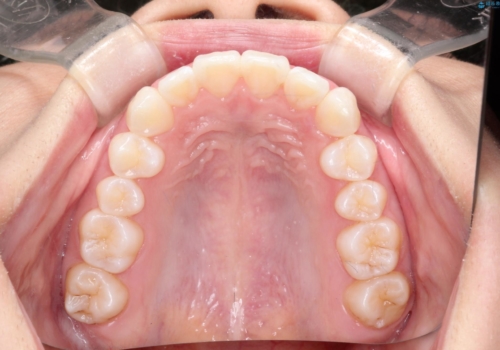

このケースでは非抜歯にて奥歯を後方に移動させる事で前歯の突出を改善するスペースを作り出していますが、これはマウスピースと顎間ゴムの併用によるもので、患者様のご協力の賜物と言えます。

深い噛み合わせについてはシミュレーション上の結果と、予期される実際の歯の移動量とを考慮し、特殊なセットアップを行う事で望ましい結果を得ることができました。

治療途中でリファインメントという追加のマウスピースを製作する手順を行っていますが、その際に上下の正中を合わせたいとの要望があったため、追加シミュレーションの際に追加でセットアップを施しましたが、無事、上下の正中もご要望通りに改善しています。

使用した装置はマウスピースと顎間ゴムのみです。ワイヤーやマイクロインプラントなど補助装置の使用はありません。